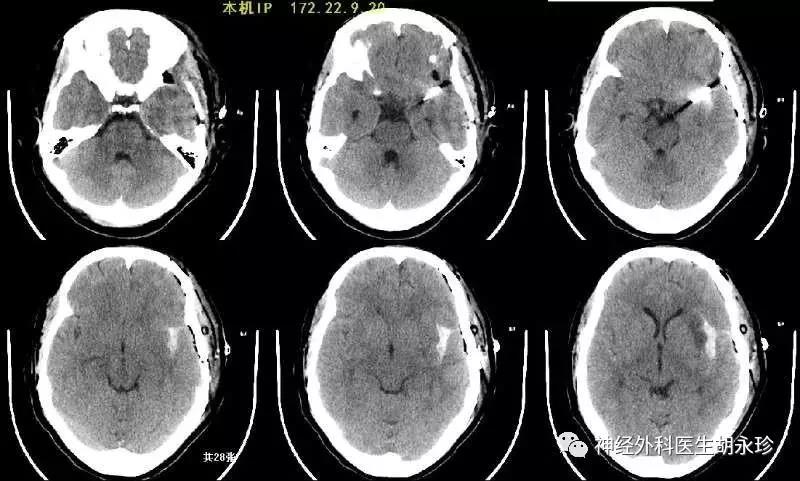

夏某,中年女性,因突發(fā)劇烈頭痛伴頭暈急診被送往外地某市級醫(yī)院救治,診斷“自發(fā)性蛛網(wǎng)膜下腔出血,左側(cè)顳葉腦內(nèi)血腫”,經(jīng)病情評估后考慮出血原因為“顱內(nèi)動脈瘤”,需要急診行手術(shù)治療。

最后患者安全轉(zhuǎn)往惠州三院,經(jīng)進(jìn)一步的評估,術(shù)前完善的檢查,了解患者無明顯手術(shù)禁忌癥后,李雪松主任向患者家屬說明病情,介紹手術(shù)方案,決定行開顱動脈瘤夾閉術(shù)。

手術(shù)過程十分順利,術(shù)中將動脈瘤安全夾閉,并將血腫予以清除,術(shù)后恢復(fù)良好,復(fù)查血管造影檢查可見動脈瘤夾閉完全,無腦梗死發(fā)生,患者及家屬很是高興。